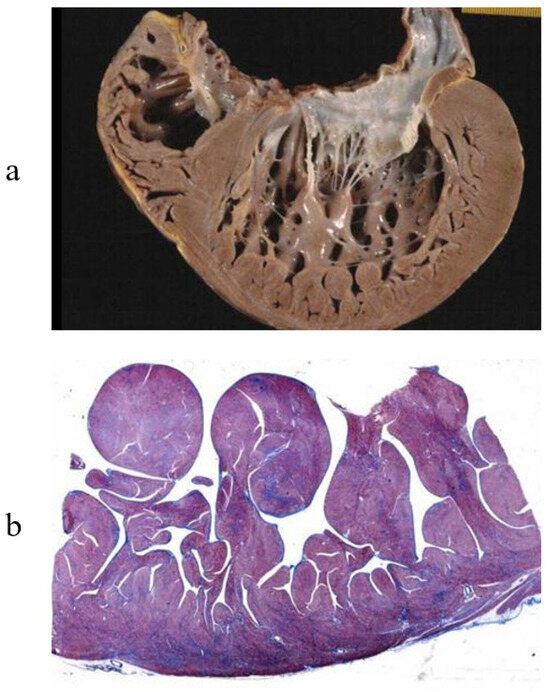

3. Arrhythmogenic Cardiomyopathy

7. Clinical Indications of Endomyocardial Biopsy

- Basso, C.; Ronco, F.; Marcus, F.; Abudureheman, A.; Rizzo, S.; Frigo, A.C.; Bauce, B.; Maddalena, F.; Nava, A.; Corrado, D.; et al. Quantitative Assessment of Endomyocardial Biopsy in Arrhythmogenic Right Ventricular Cardiomyopathy/Dysplasia: An In Vitro Validation of Diagnostic Criteria. Eur. Heart J. 2008, 29, 2760–2771. [Google Scholar] [CrossRef]